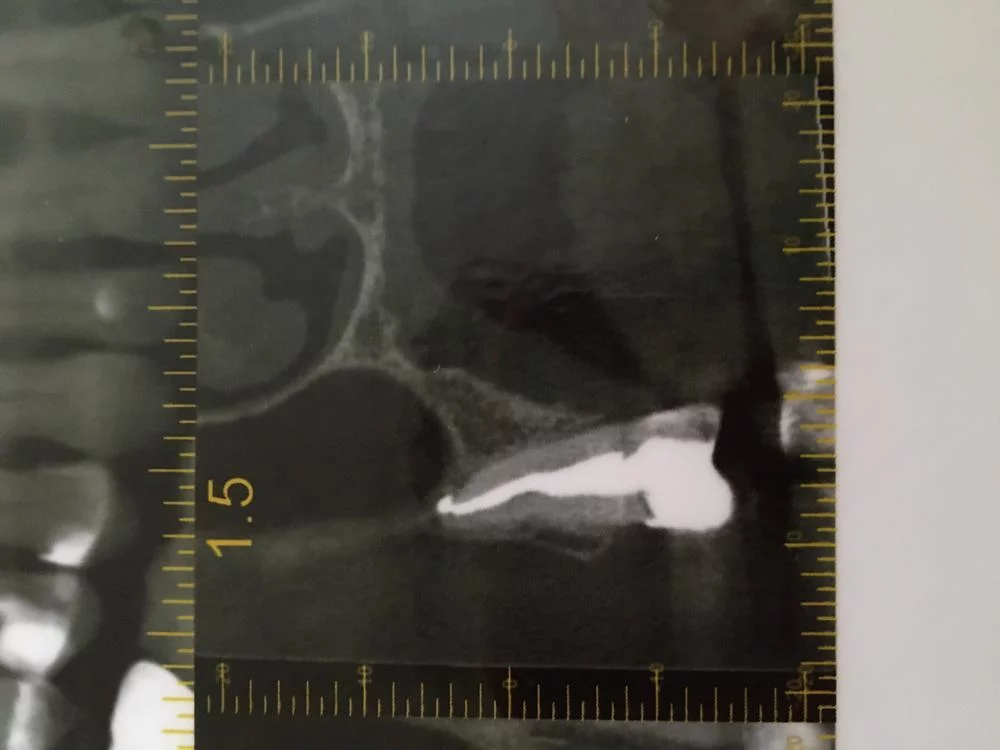

Спасибо. А что надо сделать для Диагностики? Канал пломбировали в июне. Теперь надо перепломбировать? И вообще, он хоть и не болит, но я его как то чувствую, когда языком трогаю. Пятый справа

Рентгенологически там всё спокойно: канал запломбирован адекватно, реакции со стороны околоверхушечных тканей нет.

У Вас пародонтитище. Карманы по 10 мм и сплошные камни под десной. Скорее всего, именно это даёт симптоматику.